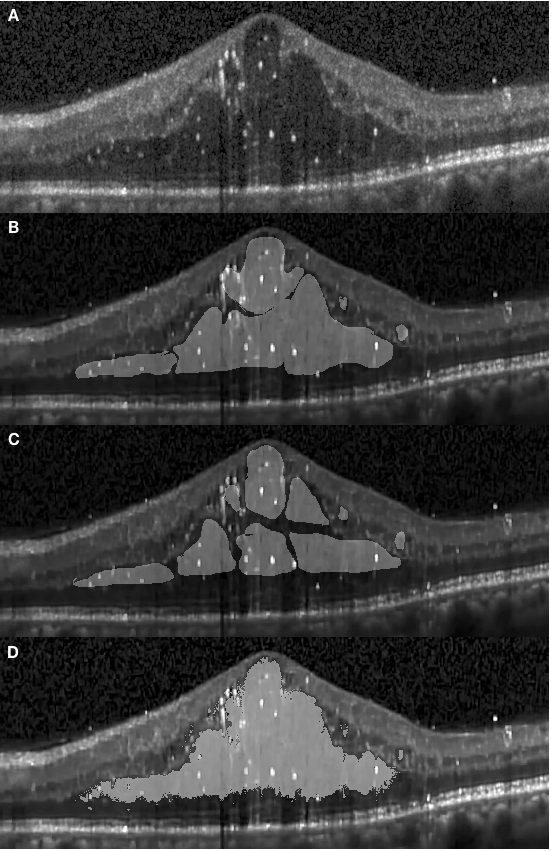

An example of an OCT retinal image exhibiting DME is shown in Fig. 2.1. The retinal layers are deformed and discrete with large cystic fluid areas embedded within the sub-retinal layers. The diabetic edema can be categorized into types: fluid and concrete. The fluid regions, embedded in various shapes and sizes, contain sparse tissue that exhibits low reflectivity. Therefore the fluid regions in the OCT images are generally shown as dark blocks surrounded by layers with high reflectivity. Conversely, the concrete regions are formed by denser tissue. The concrete area is not easily distinguishable from healthy tissue in these images, resulting in the boundary between healthy and diseased tissue not being clearly shown and segmented. Conventionally, the medical professionals segment the concrete area by subjectively estimating the thickness and delineating the boundary at what might be a reasonable position based on their experience. Therefore, different professionals may produce inconsistent results. Figure 2.2 depicts annotations obtained from two graders (both medical professionals). For example, the delineation of edema does not have a good agreement between the two manually segmented images (B and C). At the end of this article, we will show that the proposed method can objectively outperform manual segmentation in terms of consistency metrics.

In Fig. 4.3 (D) we demonstrate results of our framework operating on images depicting more severe morphological conditions. The retinal layer in Fig. 4.3 (A) was destroyed by a large section of edema which mixed various shapes of fluid and concrete edemas. The central fluid section is fused with the concrete part on both the left and the right-hand side of the images, where both sections were successfully segmented by our approach. It can be seen that our approach shows that the segmentation achieved is consistent with the appearance of the pathology and accurately covers the entire region. Several small sections were also well segmented but some slimmer region is not detected since it is too slim to be perceived by the network. In Fig. 4.5, we present additional results from severe conditions that present complex structure appearances.